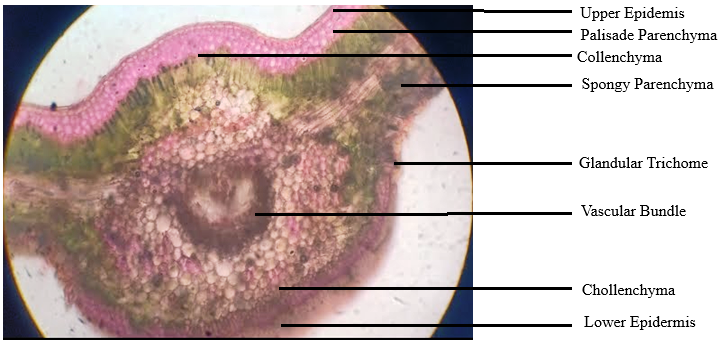

The microscopic features can serve as one of the fundamental criteria and have always made it possible to identify plant material with speed and accuracy [9]. The transverse section (TS) of the leaf part was stained twice with safranin and washed with water. It was further dehydrated using strong alcohol and ultimately put in glycerine for examination and confirmation of lignifications at 40x resolution. High-resolution images of plants have been captured using a trinocular microscope equipped with a camera, which was used to take pictures at various magnifications.

As shown in fig. 1, the microscopic observations were found to align with the reports present by (Usnale SV et al. 2009) [21]. The transverse lamina of the leaf was dorsiventral. There was only one layer of cuticle covering the top epidermis, which had anomocytic stomata. The spongy parenchymas consist of 3 to 4 layers with thin cell walls. Calcium oxalate of the druses type was found in some cells. There are single-layered palisade cells. Like the upper epidermis, the lower epidermis was single-layered and had anomocytic stomata on top of a single layer of cuticle. The upper and lower epidermis is covered by a single layer of cuticle, and the midrib has a biconvex form. Three to four layers of thick-walled cellular parenchyma make up the collenchyma that lies under the upper and lower epidermis. Some starch grains have bowl-shaped vascular bundles made of lignified xylem and phloem. There are no trichomes.

Fig. 1: TS of the leaf of Ipomoea reniformis Choisy under 40x resolutions using a Trinocular microscope